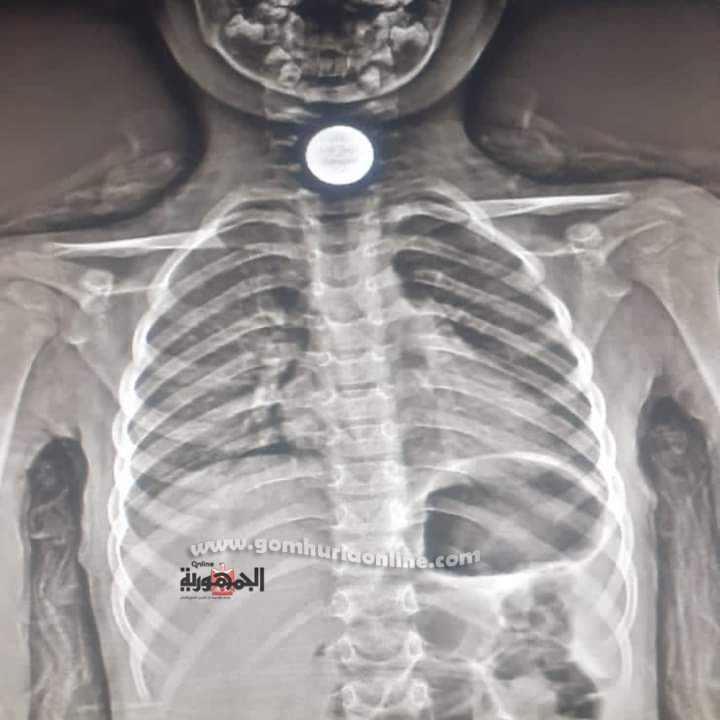

أنقذت مستشفى السويس العام حياة طفل يبلغ من العمر ٤ سنوات وذلك عقب ابتلاعه لعملة معدنية توقفت في البلعوم بين المرئ والقصبة الهوائية، وعلي الفور فقد تم استخراجها بواسطة فريق طوارئ المناظير بمستشفي السويس العام بقيادة الدكتور احمد محمد نوح  مدير إدارة المستشفيات المشرف على السويس العام والتمريض المعاون قبل دقائق من مدفع الافطار في أول أيام شهر رمضان الكريم .